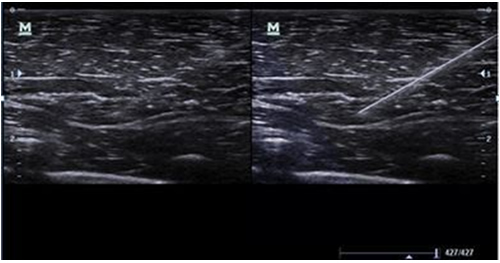

iNeedle

Инструмент для углубленной биопсии: обеспечивает регулирование отклонения УЗ-луча для улучшения видимость иглы, нервных волокон и мелких сосудов.